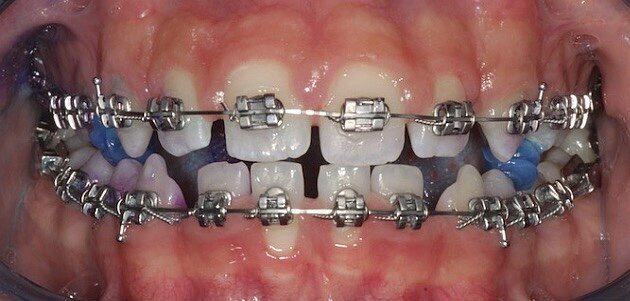

Di fatto i pazienti del gruppo I hanno riscontrato miglioramenti significativi rispetto al gruppo II, nel tempo di follow-up (Figg. 1, 2). Conclusione Prendendo in considerazione l’analisi statistica si può affermare che nella terapia di mantenimento durante il trattamento ortodontico, il dentifricio Biorepair Peribioma costituisce un valido alleato nel mantenimento dell’equilibrio microbico e della salute orale. Ruolo fondamentale nella sperimentazione è quello dell’istruzione e motivazione del paziente alle corrette manovre di igiene orale domiciliare, influenzando così il miglioramento generale degli indici. Ampiezza del campione e durata della sperimentazione costituiscono un limite dello studio, che sarà continuato e approfondito nel tempo per valutare gli effetti a lungo termine.

Fig. 1 - Case report di ortodonzia tradizionale. Fotografia frontale a t0 con rilevatore di placca.